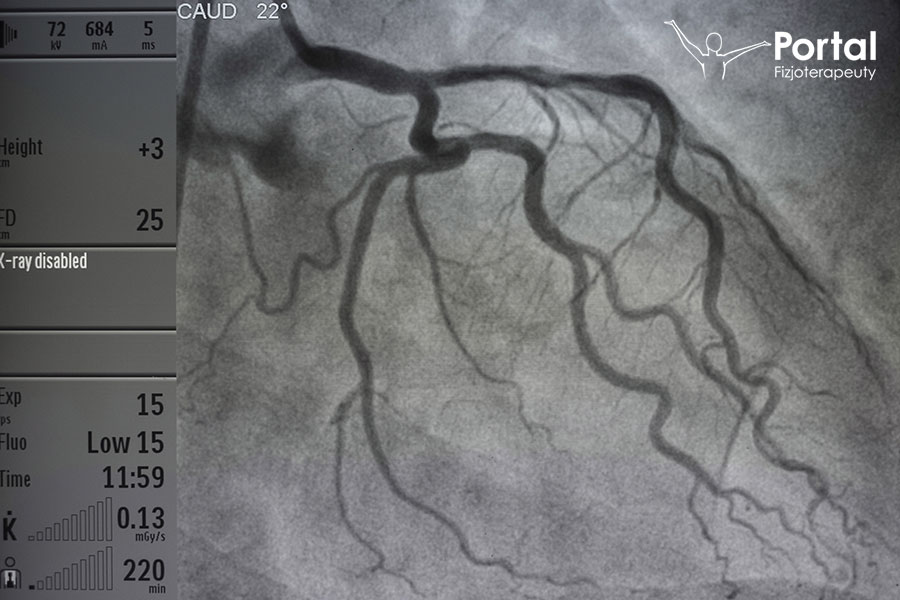

Koronarografia to podstawowe badanie diagnostyczne w kardiologii inwazyjnej i zazwyczaj pierwsza czynność rozpoczynająca proces diagnostyczno-terapeutyczny m.in. choroby niedokrwiennej serca. Zwana

Angioplastyka to zabieg kardiologii interwencyjnej polegający na udrożnieniu zwężonej bądź nawet całkiem zamkniętej zapalnie tętnicy wieńcowej. Zdobywa coraz większą popularność